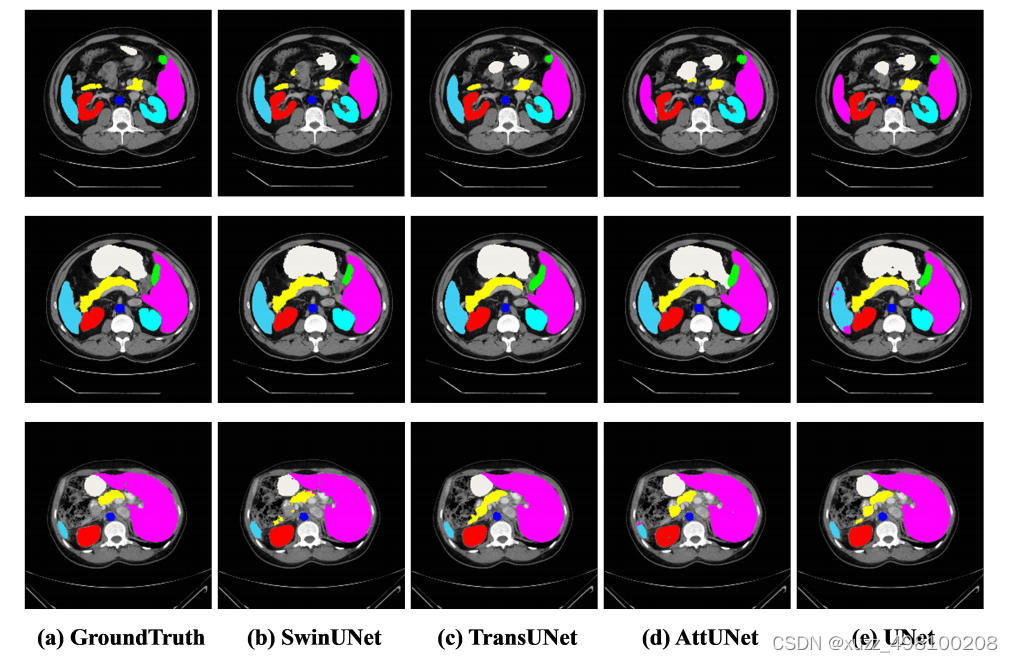

效果:

Swin-Unet凭借Swin中MSA强大特征提取能力。相比一众算法展现了sota的效果:

总结:Swin-Unet只是在各个特征提取模块将Unet的2D卷积换成了Swin结构,在Swin结构和Unet结构上基本没有改变,损失函数也没有做变化。再次说明了Swin模块的强大特征提取能力(感觉创新不太够啊,不过代码挺清爽的)